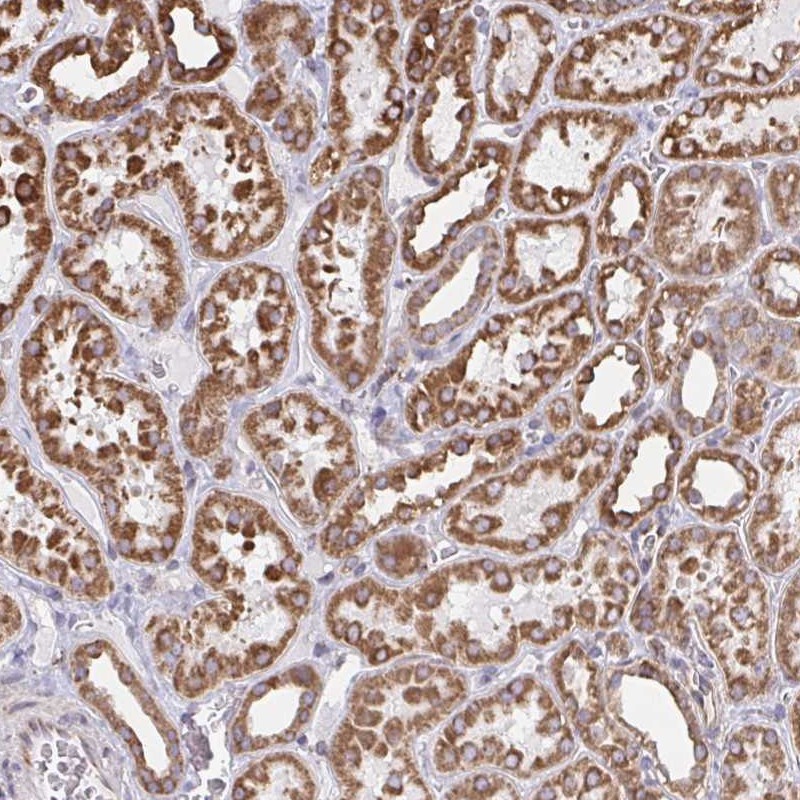

Immunohistochemical staining of human kidney shows strong cytoplasmic positivity in renal tubules.